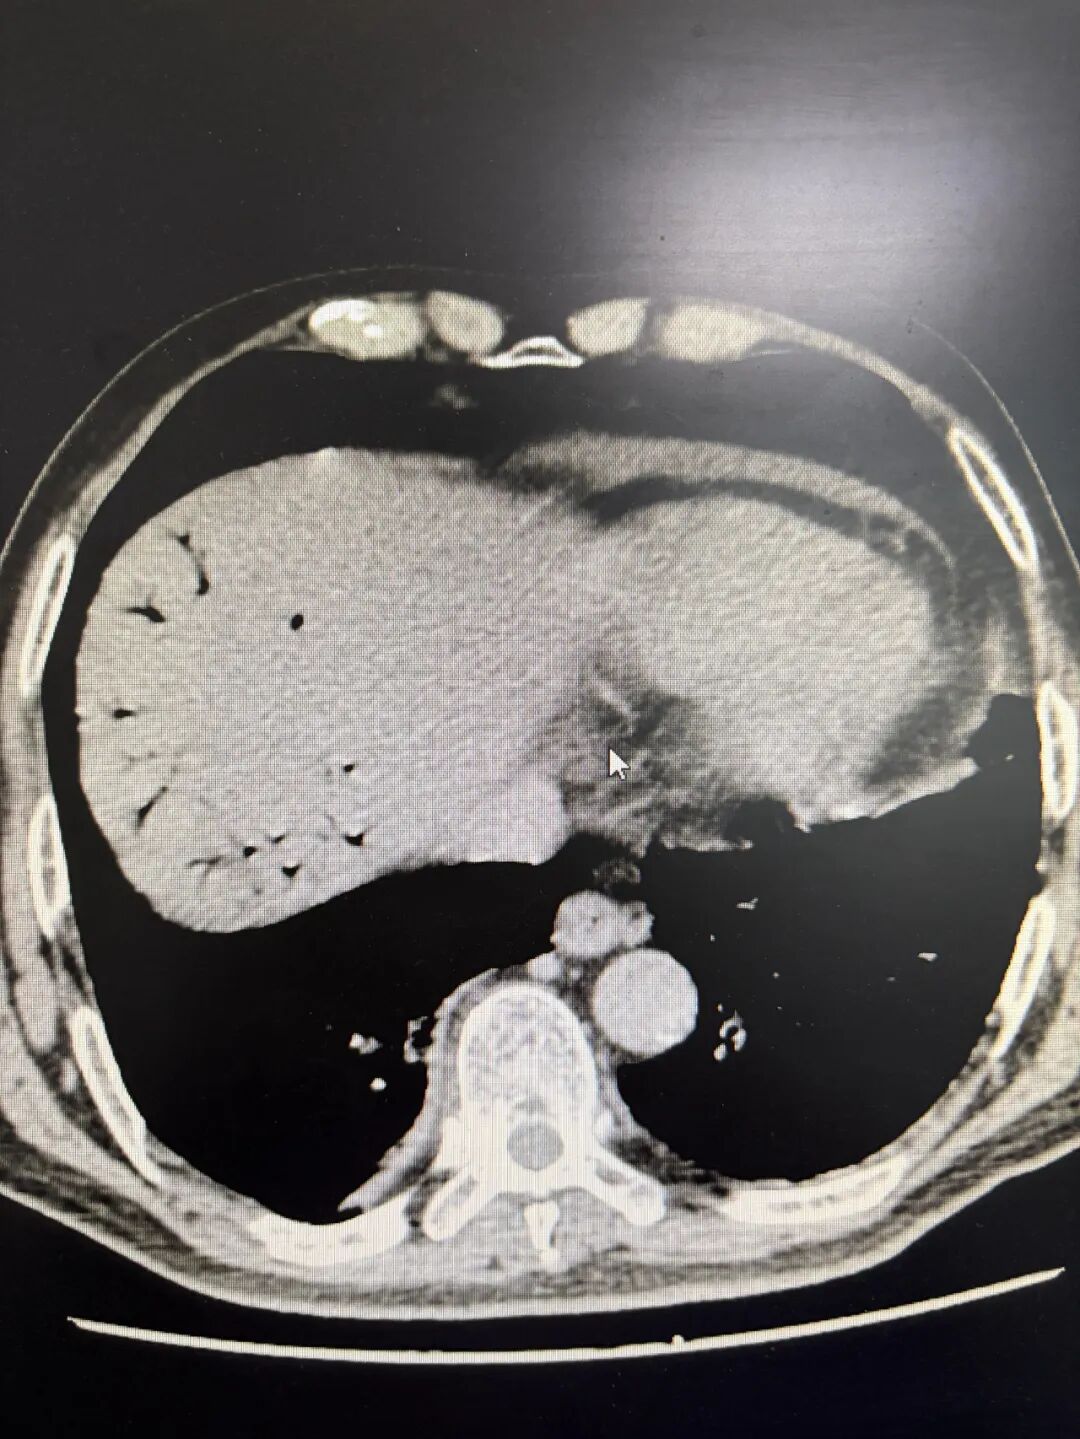

术前患者CT显示图

该患者年龄高达76岁,且既往有高血压、糖尿病病史多年,肺功能较差,加上脓毒血症的影响,极大增加了手术和麻醉难度。麻醉医师苏日娜精心配合,为手术顺利进行提供了重要保障。术中探查可见肝右叶包膜破裂出血并伴有脓液流出,与术前判断完全一致。